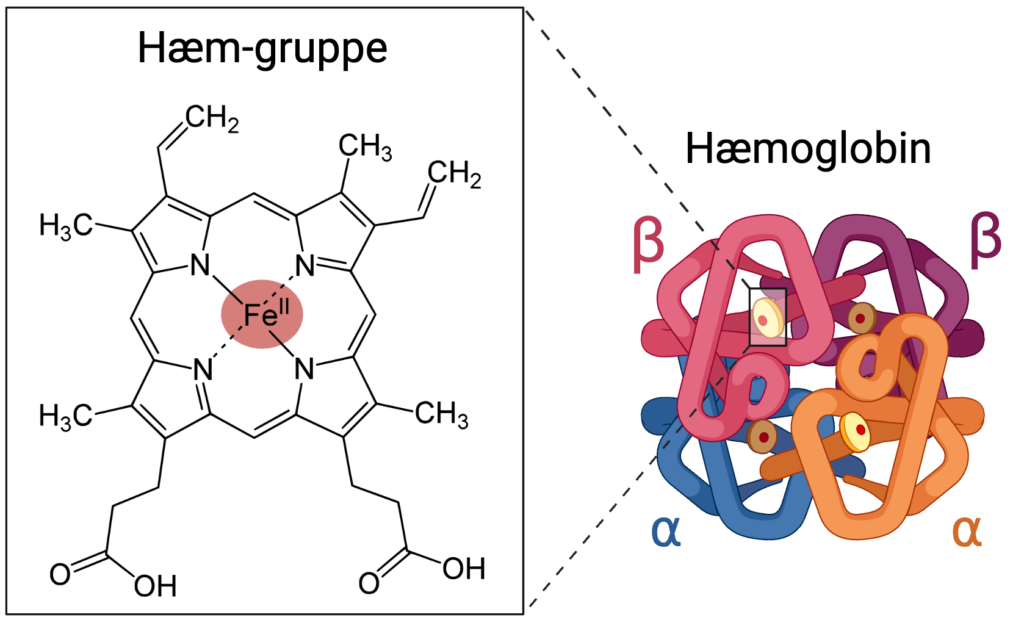

Røde blodceller er omkranset af en cellemembran af fedtstoffer og proteiner. Indeni cytoplasmaet er der over 200 millioner hæmoglobinmolekyler, som er vigtige for ilttransporten. Hæmoglobin er et protein, som består af polypeptidkæder og jernioner. Navnet ”hæmoglobin” kommer af opbygningen af proteinet, idet polypeptidkæderne kaldes globuliner, og molekylerne som indeholder jern kaldes hæm-grupper.

Der findes forskellige varianter af hæmoglobin, men den hyppigste i voksne mennesker er hæmoglobin A. Denne variant består af fire polypeptidkæder, der hver indeholder en hæm-gruppe. Tilsammen danner de en tetramer (molekyle der består af fire dele), hvoraf to af kæderne kaldes a-kæder, og de andre to kaldes b-kæder. Opbygningen af hæmoglobin ses på figur 2.

Jernionerne i hæmoglobin er det sted, hvor ilten bindes, når den transporteres rundt i kroppen. Når ilt ikke er bundet, indeholder hæm-gruppen ionen Fe2+ (ferrojern). Så snart ilt bindes, oxideres jernionen til Fe3+ (ferrijern), og den kan ikke binde yderligere iltmolekyler, før den er reduceret tilbage til Fe2+.